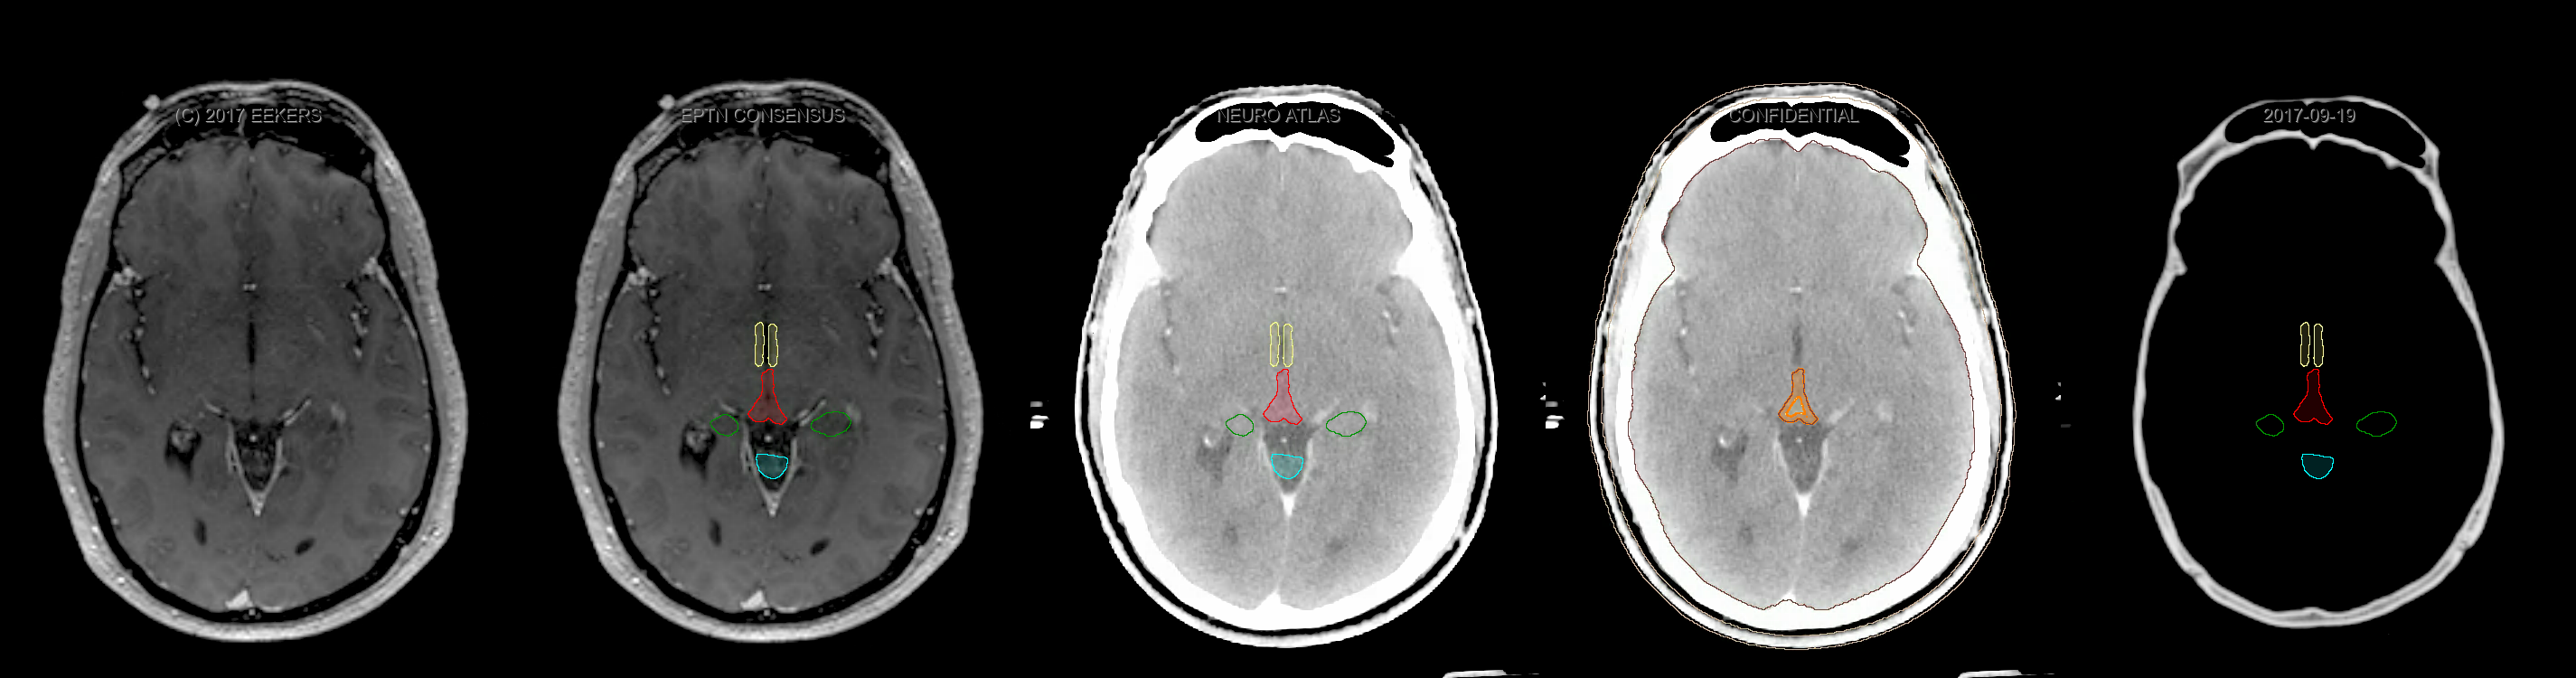

Three-dimensional delineation of the fifteen consensus OARs for neuro-oncology are shown on CT and 3 Tesla (3T) MR images (slice thickness 1 mm with intravenous contrast agent). All are presented in transversal, sagittal and coronal view.

From left to right: MR without structures, MR with structures, CT (WW/WL 120/40) with structures, CT (WW/WL 120/40) with Brain and Brainstem Surface, CT (WW/WL 1500/120)with structures